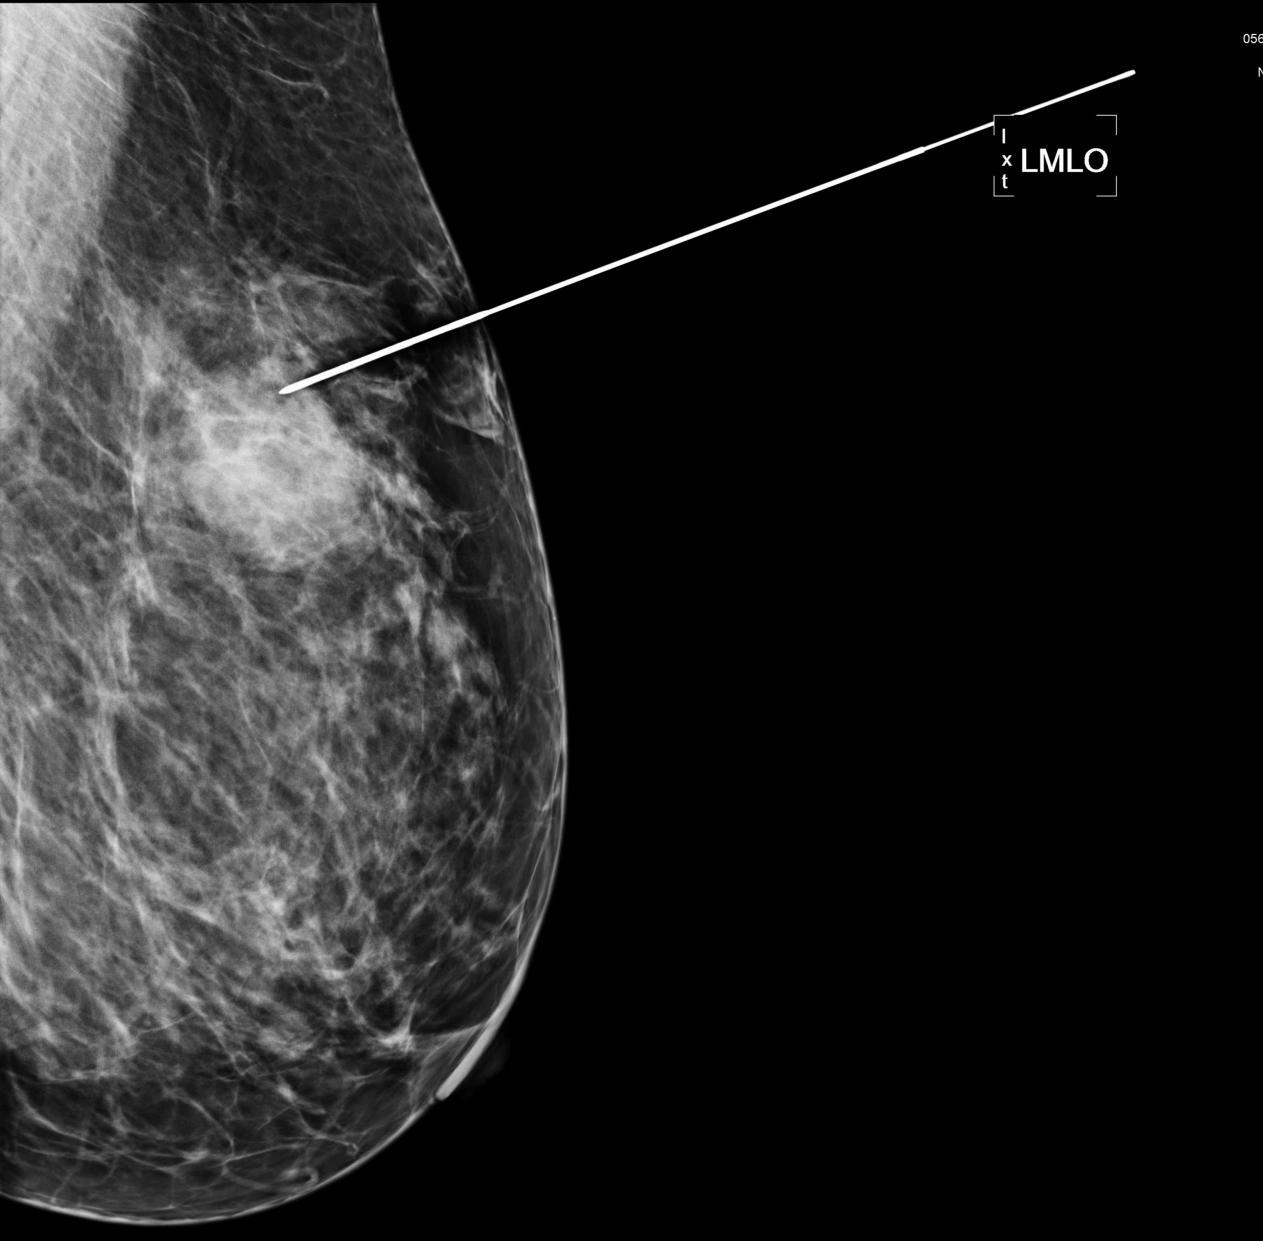

54岁的赵女士因乳腺疼痛不适,曾多次进行乳腺彩超检查,但未发现明显肿块,近日因胃部不适于来我院就诊,住院后进行胸部CT检查发现左乳占位,乳腺钼靶检查显示左乳外上象限肿块,外缘模糊且有分叶,BI-RADS分类4A。查体双乳未触及明显肿块,彩超也无法准确定位。结合患者病史、体检及相关辅助检查,与患者及家属充分沟通后,我院甲乳外科二病区医疗团队决定对其行钼靶定位引导下乳房肿块切除术。

▲术前钼靶

术前,我院甲乳外科二病区林明副主任医师和北区放射科刘璇婷主治医师共同查阅了赵女士的钼靶影像资料,术中,根据钼靶定位结果,完整切除了肿块,手术获得成功,目前患者已经康复出院。此例钼靶引导下定位技术属皖东地区首例,填补了皖东地区该项技术空白。